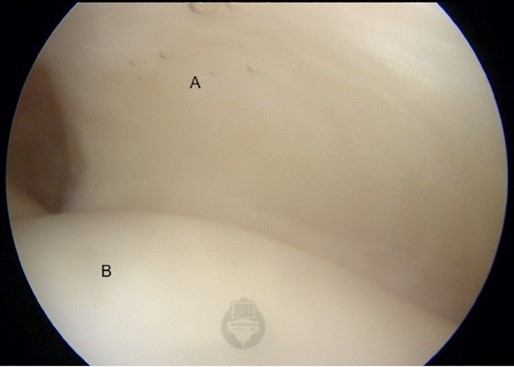

The rotator cuff tendons tear at their insertion into the humerus.  If a tear in the tendon goes through the full depth of the tendon then it is called a ‘full-thickness tear’.  If the damage involves only some of the thickness, it is termed a ‘partial-thickness tear’. Both can be painful and, because of this pain, impair function.  Full thickness tears tend to cause more significant weakness, as the connection between the muscle’s force and the bone is interrupted. The first image below shows a normal supraspinatus tendon (A) as it inserts onto the humeral head (B). The next two views show a medium-sized rotator cuff tear.  note how the tendon has peeled off from its insertion on the humerus, leaving exposed bone

Arthrosopic view from within shoulder joint - (A=Supraspinatus. B=Humeral head)